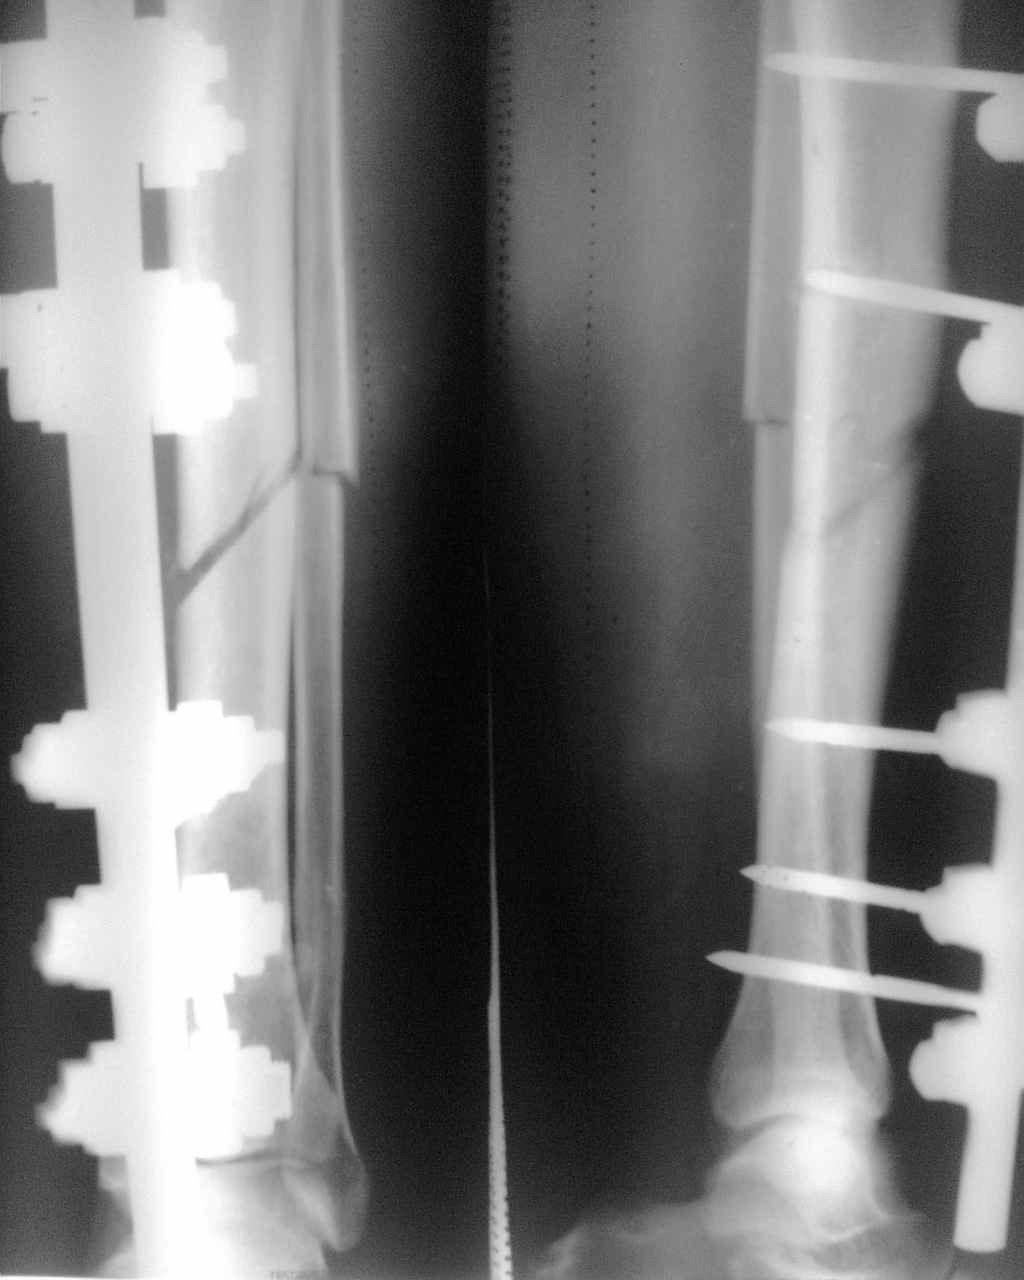

Снимок прилагается

Кликните для загрузки файла Фото005.jpg

Мне кажется, что в данном случае, конечно, есть какой-то дефект (как при любом распиле), но отдельно учитывать его величину не стоит и нужно просто заштифтовать как самый обычный перелом.

Согласен с Ю.А. Булахтиным. Учитывая толщину обрезного круга и рентгенологическую картину, величина дефекта не потребует дополнительного вмешательства на малоберцовой кости. При закрытом БИОС рассверливание канала даст достаточный материал для образования костной мозоли. Каково сейчас состояние мягких тканей? Если заживало первично, то в чем причина длительного периода АВФ? Организационная? Если не было признаков нагноения в зоне стержней – почему не одномоментно демонтаж АВФ и БИОС? Если я Вас правильно понял, б\б кость не распилена полностью. Таким образом даже при остеотомии м\ б кости(сегментарной резекции) Вы не достигнете «схлопывания »дефекта за счет интактной заднее – латеральной стенки. Вы хотите интраоперационно выполнить остеоклазию? Мой выбор - БИОС с рассверливанием канала, динамизация по результатам рентгенографии (через 6-8 недель )

Полностью разделяю мнение доктора из Ярославля. Зачем огороды городить, резекция здесь не нужна, зажившую зону перелома тоже ворошить не надо. Статическая блокировка с рассверливанием, нагрузка, мозоль на рентген-контроле как вариант динамизация, хотя не обязательно.